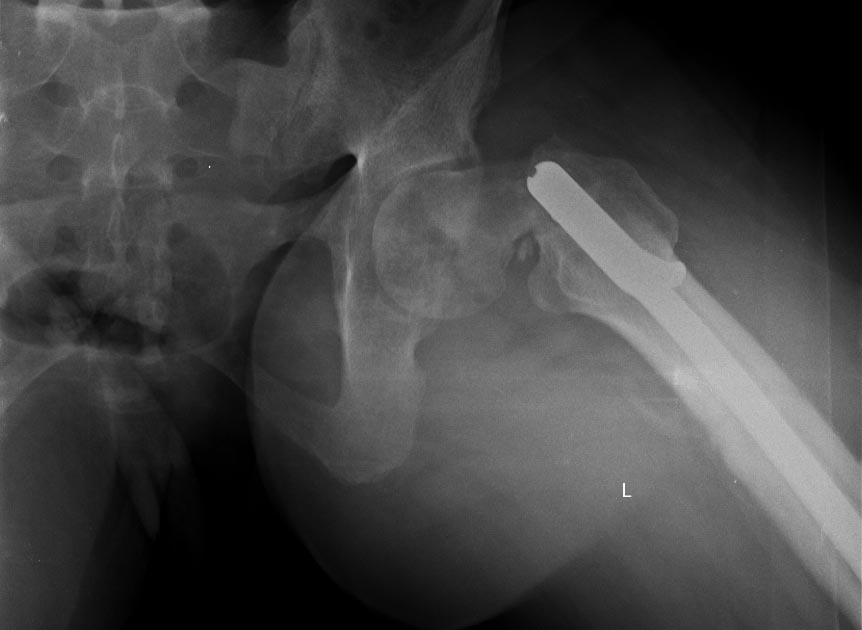

Александр Николаевич, любая попытка сохранить сустав у молодого пациента приветствуется. Смущает ограниченный контакт в зоне перелома, все же надо иметь ввиду несвободную костную пластику на питающей ножке в случае если через1,5-2 месяца Вы не увидите намеков на консолидацию.

Александр Николаевич, вопросы абсолютно справедливые. Предпочтение отдаются участку крыла подвздошной кости на мышечной ножке. Трансплантат располагается по передней поверхности шейки бедренной кости (во всяком случае там, где она должная быть) слегка внедряется в головку и шейку и фиксируется одним винтом в дистальном отделе в зоне б/вертела. Доступ к суставу проходит между мыщцами и достаточно мало травматичный. На эту тему в институте была защищена диссертация Карелкиным Виталием Вл-чем, в работе детально проработаны все анатомические нюансы забора трансплантата. Что касается нагрузки.... Эвакуация от себя это правильный принцип))) но ведь и позвонить могут... Если по сути, то действительно сложно оптимизировать нагрузку, но и без нее нельзя. Я бы разрешил первые 6 недель с касания пола до веса ноги. Последующая постепенная нагрузка до одного костыля к 4-м месяцам, далее - по ощущениям в зоне комфорности. Избыточная нагрузка опасна, длительная иммобилизация ничего не даст. Контрольная Р-грамма через 2-а месяца, необходимо оценить два момента - смещение имплантата и наличие признаков мозолеобразования. При отсутствии смещения и признаков регенерации целесообразна костная пластика. При наличии миграции имплантата - протезирование.... и далее по тексту. Сроки конечно могут варьировать, но не думаю что очень сильно.